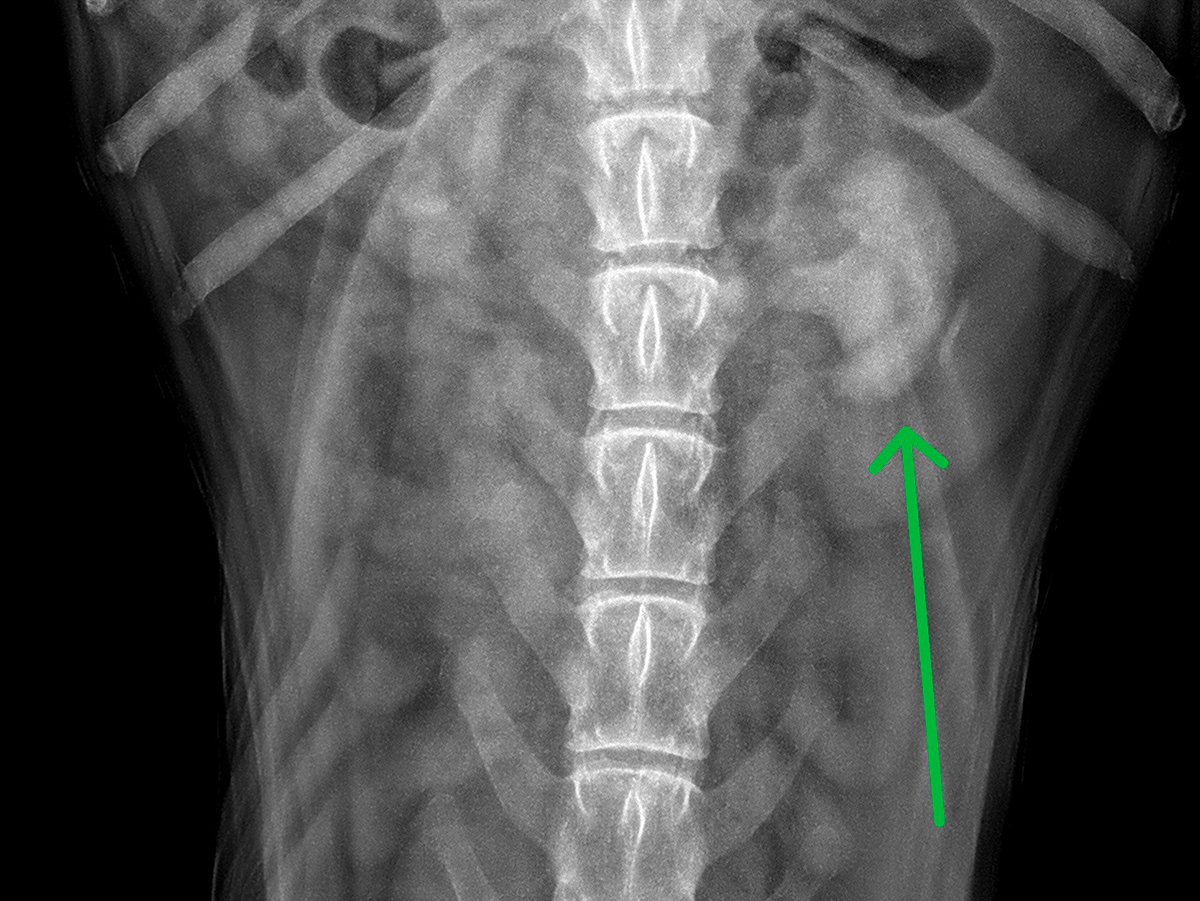

Neurochirurgie

Scanner